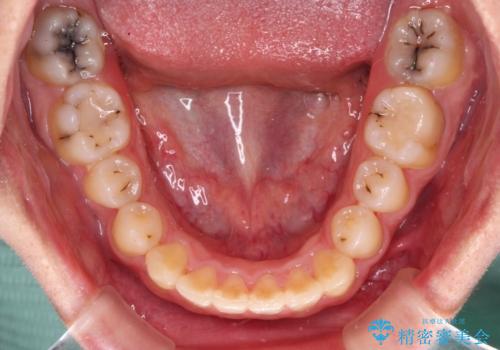

- 前歯のクロスバイトと、大学生のころから放置している虫歯を気にして来院された患者様です。

マウスピースでの矯正治療を希望されていましたが、前歯のクロスバイトは不十分な仕上がりや歯髄壊死などのリスクが高くなるため、術前にワイヤーで大まかに整えてからインビザラインにて矯正治療を行うこととしました。

奥歯の虫歯は抜歯が必要であったので、矯正治療前に抜歯をし、矯正治療と並行してインプラントによる補綴治療を行うこととしました。